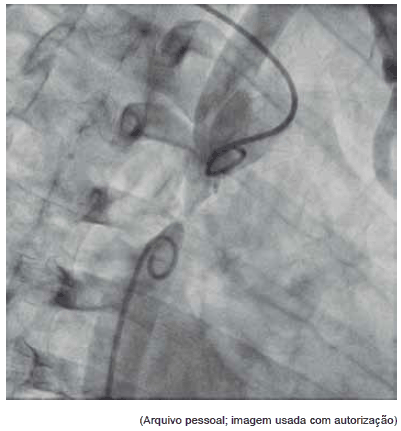

Esta angiografia diz respeito a:

Provas